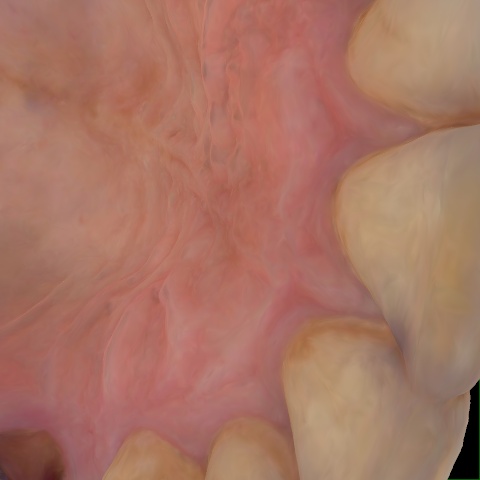

Image 361 / 1743

NHD36692

Annotated as "Good"

Original Image Rendering Image